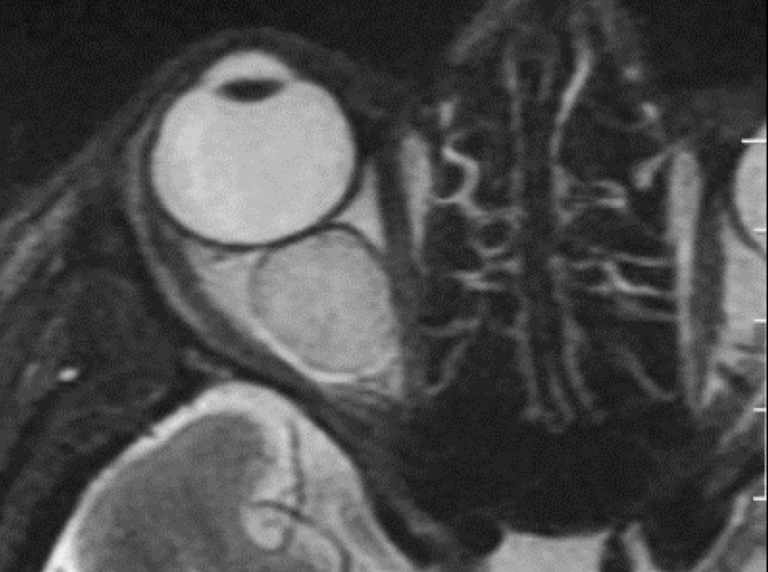

Q

¿de qué enfermedad nos hablan las siguientes imagenes?

A

Retinoblastoma cuadrilateral